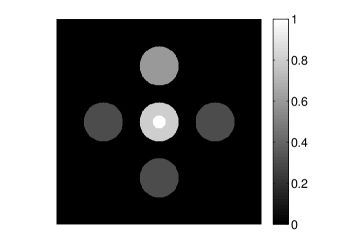

The numerical phantom shown in Figure 1(a) was employed. The phantom had a support area of mm2 and contained six uniform disks that were assigned different values of absorbed optical energy density.

A 2D circular measurement geometry was employed. transducers were evenly distributed on a ring of radius mm that enclosed the phantom. The SOS was assumed to be constant and set at mm/s. Since the simulated data were formed by use of the C-D imaging model in Eqn. (2), no inverse crime was committed. The components of this vector corresponded to equally spaced temporal samples over the interval s. Subsequently, the noiseless voltage vector was obtained by convolving the pressure data with EIR-1 in Figure 1(b).

The reconstruction region ( mm2) was represented by pixels with pixel size mm in each dimension. The initial guess of the EIR employed in the VP algorithm was different than the EIR that was assumed when generating the simulated data. This served to simulate a situation in which an experimentally measured EIR contained errors.

Each element in a real-world transducer array possesses its own EIR. In practice, the differences between the EIRs are sometimes neglected and an EIR corresponding to a single element may be used to represent all elements in the array. In some of the studies below, the EIR employed to initialize the VP algorithm (EIR-2 in Figure 1(b)) and the EIR employed to produce the simulated measurements (EIR-1 in Figure 1(b)) were experimentally measured from two different transducer elements in a circular transducer array (see Sec. VI-B). EIR-1 was measured by temporally integrating the PA signal produced by a point source positioned at the focus of the transducer. EIR-2 was measured by use of the method reported in [RNR2011]. In order to investigate the sensitivity of the VP algorithm to the initialization of the EIR, we employed different EIRs obtained by degrading EIR-1 as described later. When solving the sub-problem in Line-2 of Algorithm 1, was initialized as the zero vector. Algorithm 1 was terminated after 500 iterations, since it was observed that the changes in the reconstructed images with more iterations were negligible. When implemented by use of a single core of an Intel Xeon E5-2640 CPU, each iteration required approximately 7s to complete.

Figure 2(a) shows the image reconstructed by use of the conventional iterative method that utilized a system matrix based on EIR-2. Different values of the regularization parameter from the interval were considered. The reconstructed image with the value of that minimized the RMSE was chosen to represent the best performance of the conventional iterative method. Figure 2(a) and the profile in Figure 2(c) demonstrate that the use of an inaccurate EIR can result in strong artifacts and distortions in images reconstructed by use of the conventional methods.

When the VP algorithm was applied, different values of the regularization parameter from the interval and from the interval were considered. The image that minimized the RMSE was chosen and displayed in Figure 2(b). As revealed by this image and the profiles in 2(c), the VP algorithm yielded an image with fewer artifacts and distortions, and image fidelity was improved as reflected by the reduced RMSE.